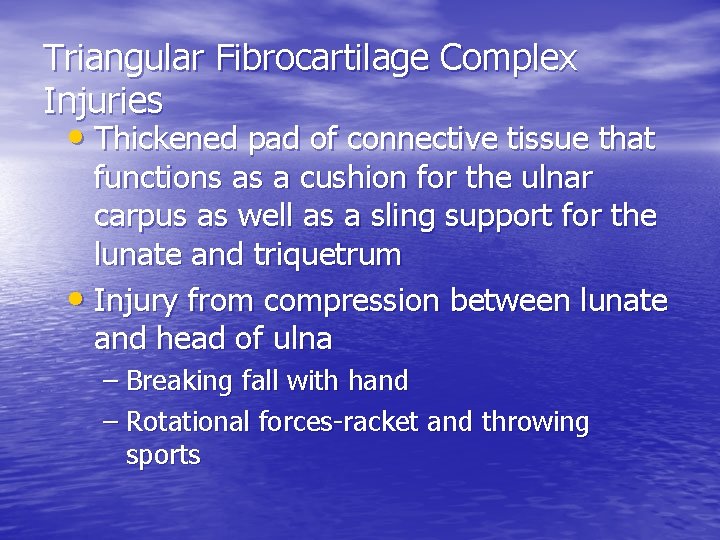

Triangular Fibrocartilage Complex Injuries • Thickened pad of connective tissue that functions as a cushion for the ulnar carpus as well as a sling support for the lunate and triquetrum • Injury from compression between lunate and head of ulna – Breaking fall with hand – Rotational forces-racket and throwing sports